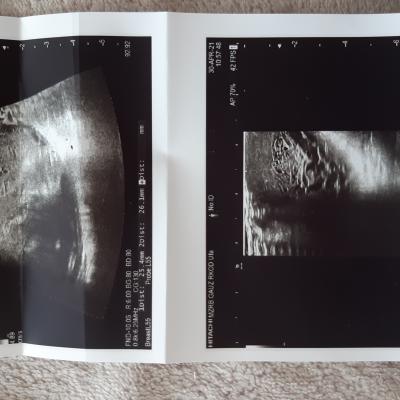

Здравствуйте! В первую очередь - сделайте повторное УЗИ органов мошонки и подвздошных сосудов и лимфоузлов. С результатами - покажитесь лечащему урологу очно, согласуйте с ним тактику дальнейшего обследования и лечения, обсудите целесообразность выполнения анализов крови на – хорионический гонадотропин человека (ХГЧ), альфа – фетопротеин (АФП), лактатдегидрогеназа (ЛДГ). Обязательно очно наблюдайтесь у врача. Удачи!